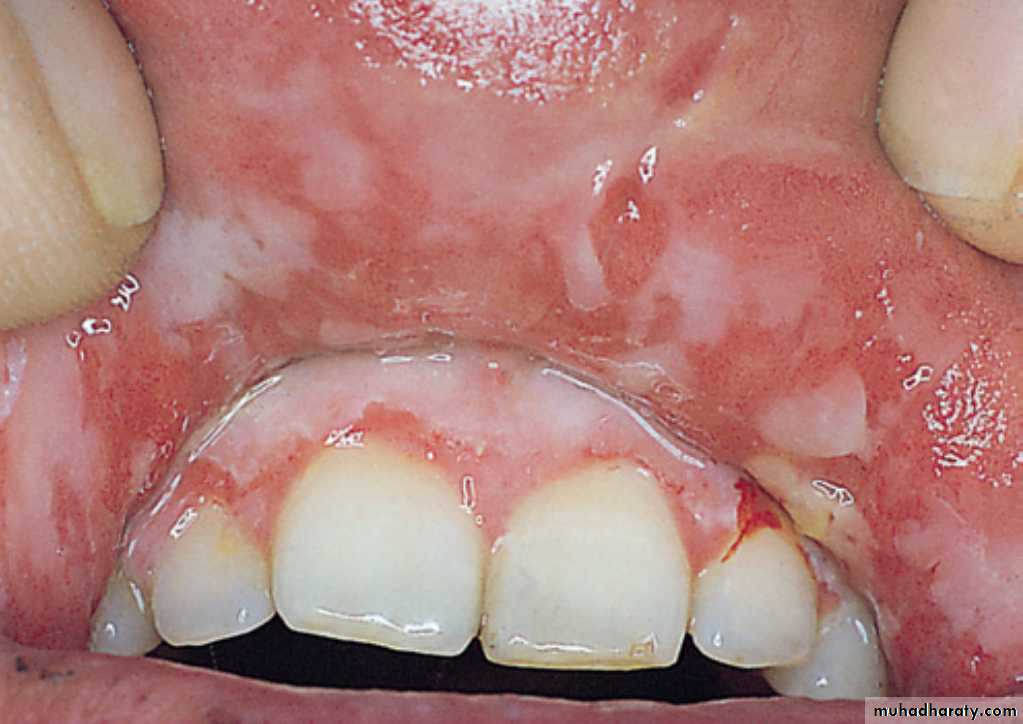

There is ulceration, erythema, sloughing of epithelium and a small vesicle centrally. The anterior part of the mouth and the lips are typically affected.Erythema Multiforme